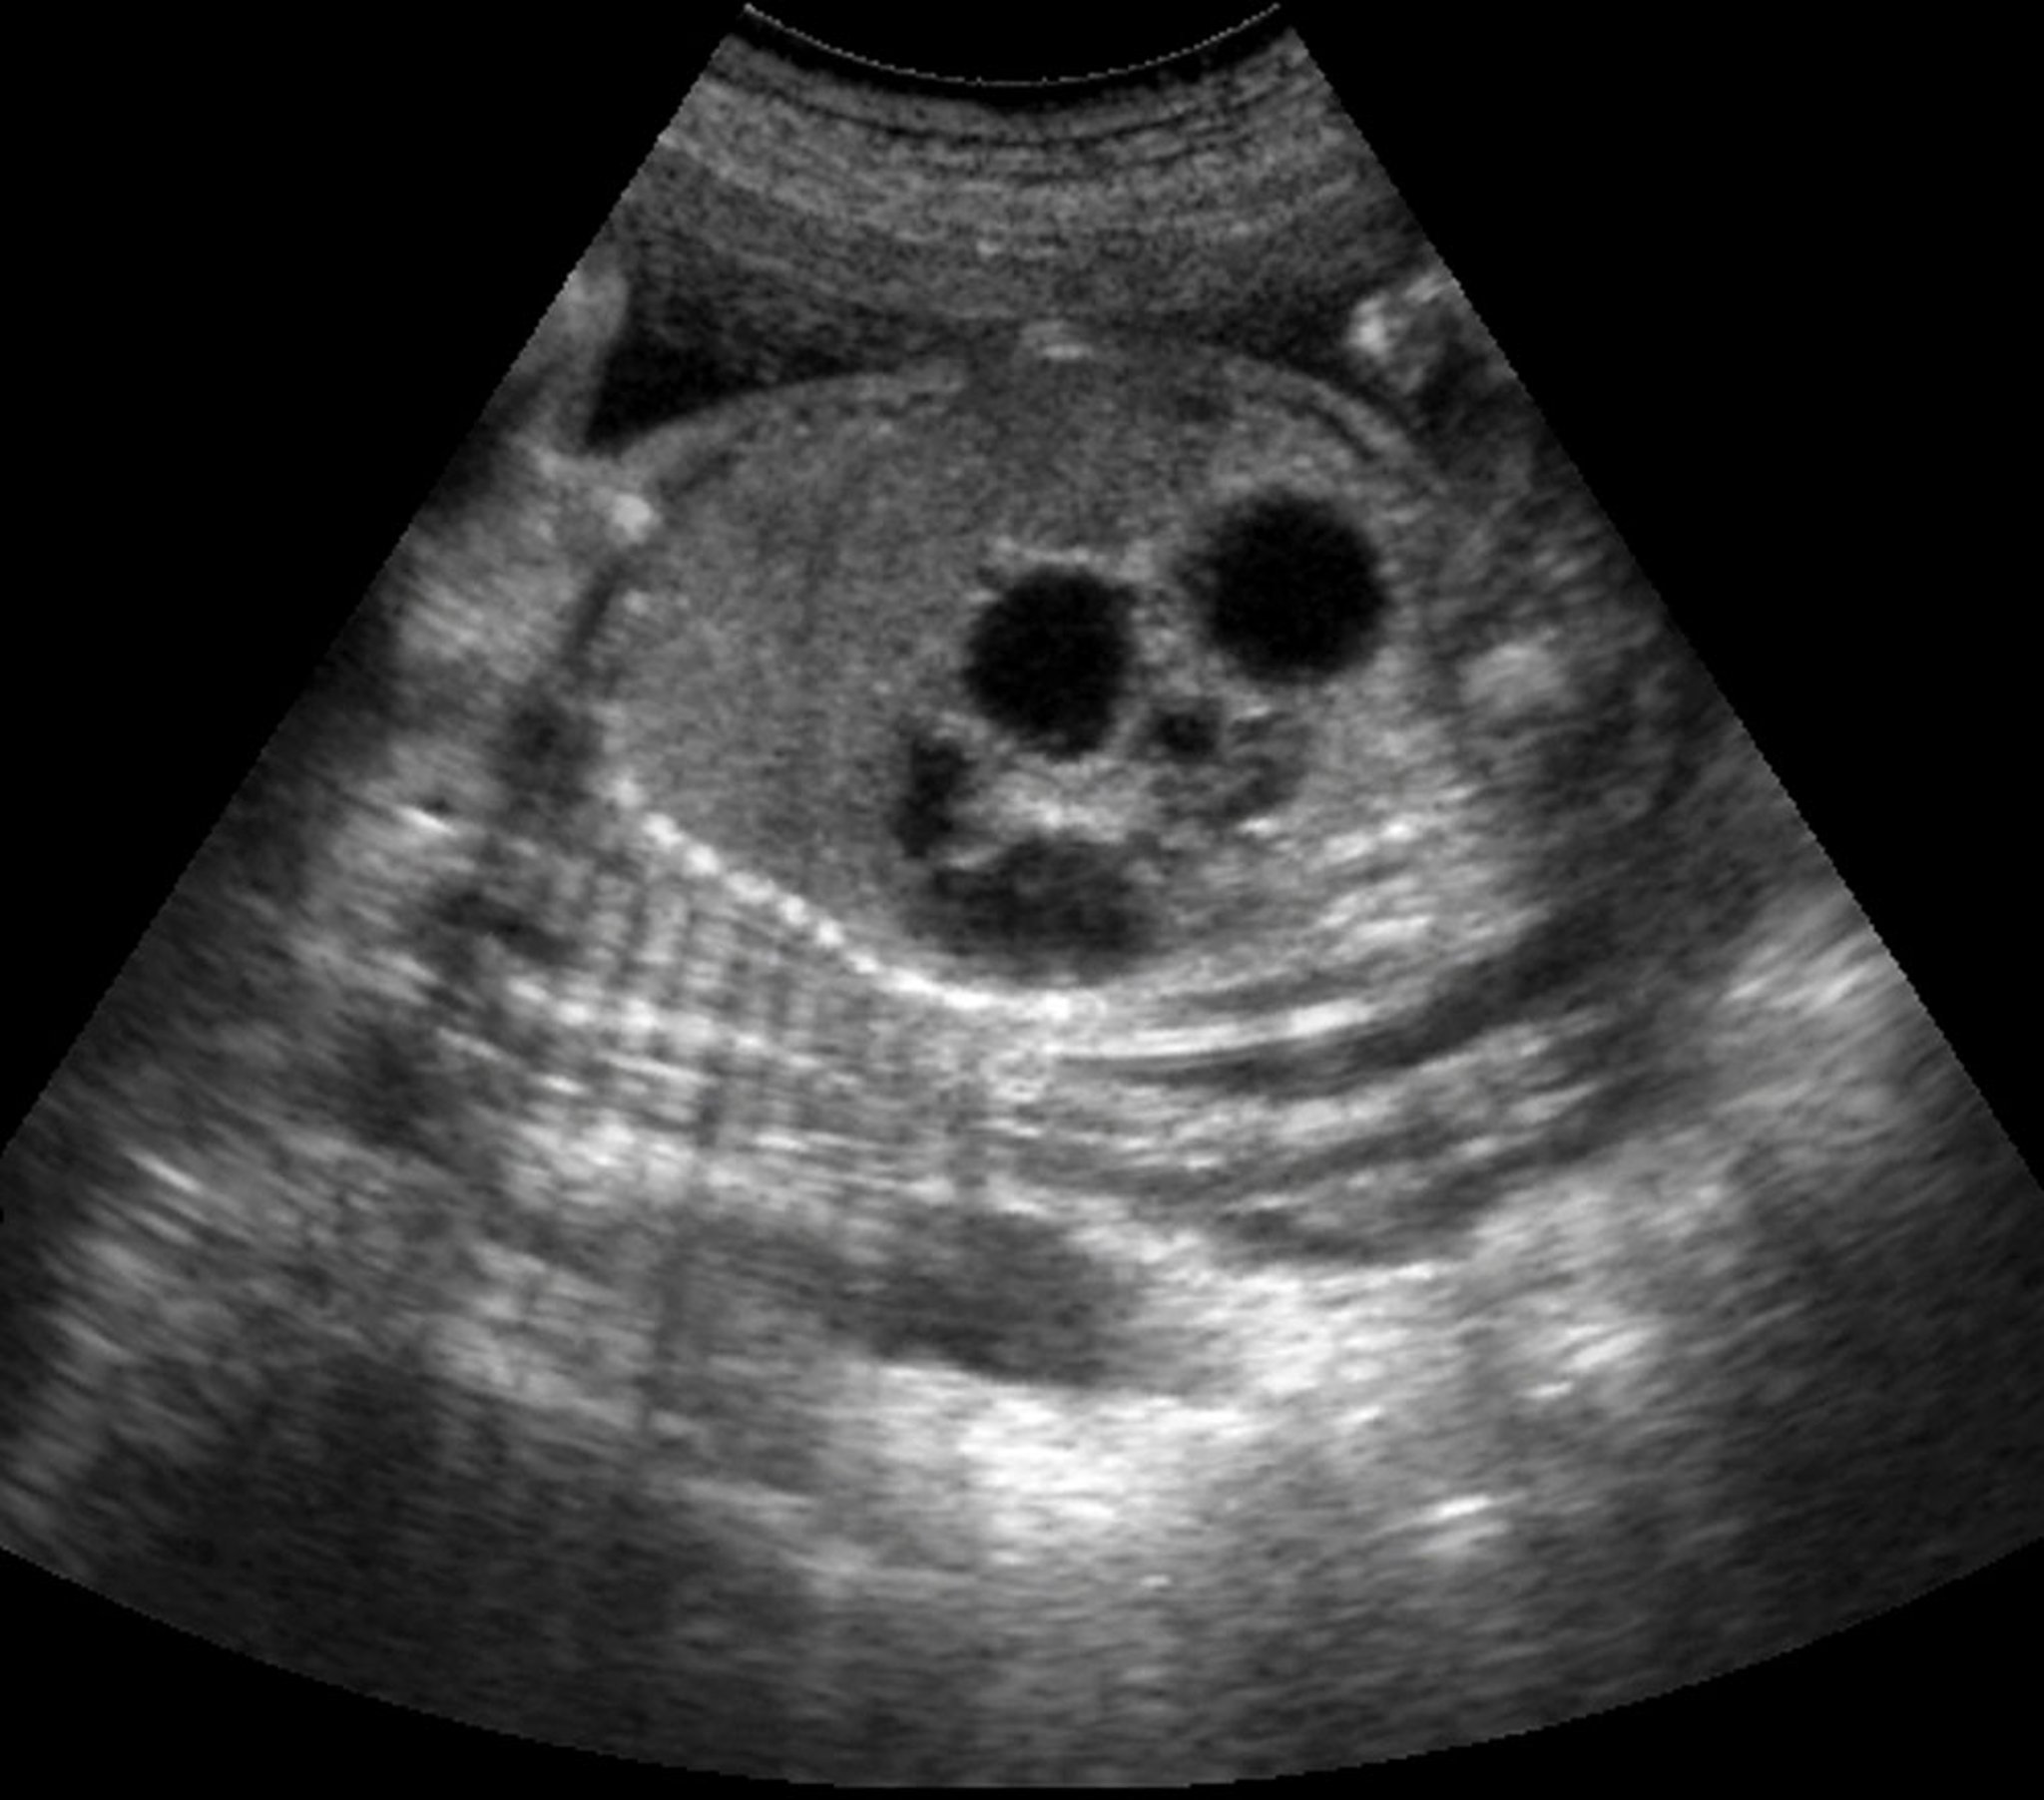

Efeito de dupla bolha (ultrassonografia)

Esta ultrassonografia mostra o sinal de bolha dupla em um feto com atresia duodenal.